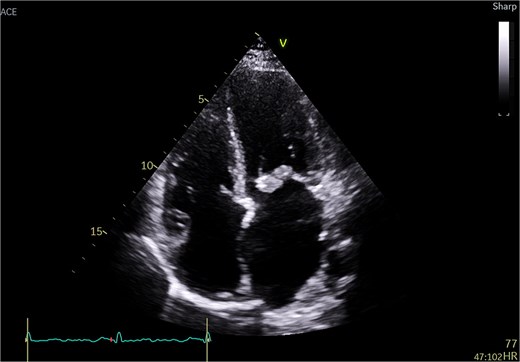

A 51-year-old woman with history of hypertension, hyperlipidemia, diabetes mellitus type II, previous ablation for supra ventricular tachycardia with implantation of loop recorder and sleeve gastrectomy for obesity was referred for surgical evaluation of MR. She was non-smoker with positive family history of ischemic heart disease affecting her mother. She was investigated for recurrent strokes with left sided paresthesia in 2022 and right sided paresthesia with dysarthria in 2024. She had dyspnea on minimal exertion and lower limb edema but no hemoptysis. She had one miscarriage previously with no history of deep vein thrombosis or pulmonary embolism. She had no history of myalgia, arthralgia, and no photosensitivity. Transthoracic echocardiography (TTE) showed pulmonary hypertension with moderate tricuspid regurgitation (TR) and moderate to severe MR and severe mitral stenosis (MS). The appearance was suggestive of rheumatic disease (Fig. 1). Trans esophageal echocardiography (TEE) showed severely dilated left atrium (LA) with no thrombus. Mitral valve with thickened with tethered posterior leaflet with mean gradient (MG) of 13 mmHg. Severe MS and moderate MR with large mass attached to the posterior scallops (Fig. 2) measuring 20 × 15 mm (likely thrombus). Ejection fraction was 55%. She was in sinus rhythm persistently and afebrile. Coronary angiography was normal. She was commenced on oral anticoagulation (Warfarin) for the possible thrombus, and she was reluctant for surgery. Her blood work was normal including normal complete blood count and renal, liver, and thyroid profile with therapeutic international normalized ratio (INR). Blood cultures were negative for growth. She was seen by haematology and work up revealed APS with a recommendation for lifelong warfarin. Patient subsequently accepted surgery.

Transthoracic echo appearance of mitral valve with mass attached to posterior leaflet (apical 4 chamber view).